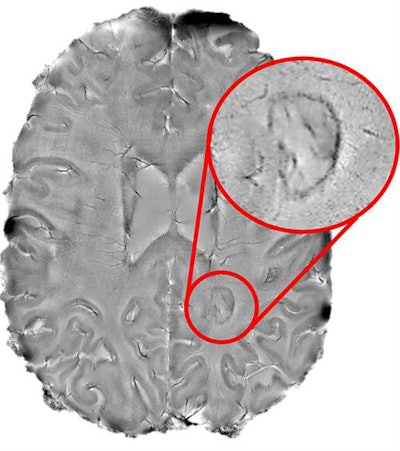

The ultrahigh field strength of 7-tesla MRI has proved effective in identifying otherwise difficult-to-find lesions in the brains of patients with MS -- leading to new insight into the relatively elusive disease. Of note, recent research from the U.S. National Institutes of Health (NIH) linked the presence of dark-rimmed spots, or chronic active lesions, on 7-tesla MRI scans with various disabilities in individuals affected by MS.

Expanding upon this earlier research, Absinta and colleagues investigated the long-term relationship between chronic rim lesions detected with 7-tesla or 3-tesla MR imaging and MS-related disabilities in 192 MS patients. Approximately 34% of the patients had one to three chronic rim lesions and 22% had at least four rimmed lesions, despite receiving conventional drug therapy.

Advanced MR imaging enabled the detection of chronic active lesions and thereby helped determine which patients with MS were most susceptible to aggressive forms of the disease, said senior investigator Dr. Daniel Reich, PhD, director of the NINDS translational neuroradiology division.